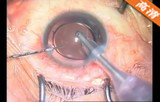

2.2mm微切口白内障超声乳化+人工晶体植入手术

该手术做2.2mm角巩膜缘主切口及侧切口; 前房注入医用透明质酸钠; 连续环形撕囊; 水分离、水分层;超声乳化核和核壳 ,注吸皮质; 抛光前囊和后囊; 前房及囊袋内注入透明质酸钠凝胶; 植入折叠人工晶体; 吸除透明质酸钠凝胶; 水密切口。

关键词: 2.2mm微切口 白内障 超声乳化 折叠人工晶体